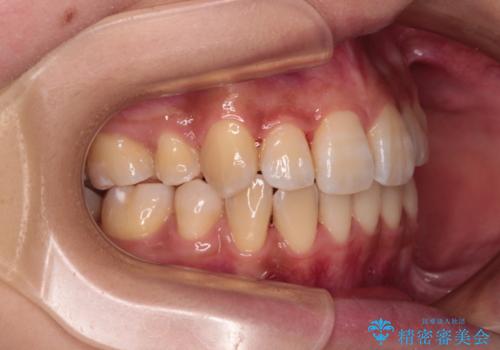

- 前歯のデコボコやクロスバイトと上顎の前突感による口の閉じにくさを気にして来院された患者様です。

目立たない装置を希望されたので、上顎が裏側装置のハーフリンガルを選択し、上下左右の小臼歯(計4歯)を抜歯して矯正治療を行うこととしました。